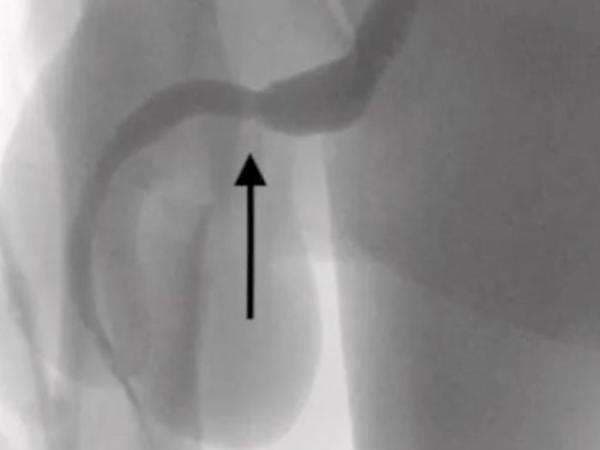

"Dua port distal dari kabel USB ditemukan menonjol dari meatus uretra eksternal sementara bagian tengah dari kabel yang diikat tetap berada di dalam uretra, demikian lapporan itu mengutip Indy100 , Senin (5/9/2022).

"Sayatan peno-skrotum memanjang di atas benda asing yang teraba dibuat dan pembedahan hati-hati dilakukan melalui jaringan yang lebih dalam, membelah otot bulbospongiosus. Kedua ujung kawat berhasil ditarik keluar melalui meatus uretra eksterna," begitu isi laporan.

"Kedua ujung kaebl berhasil ditarik keluar melalui meatus uretra eksternal," lanjut laporan tersebut.